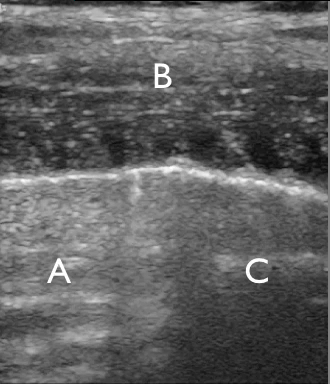

Ultrasound clip demonstrating a “lung point,” where the transition between pneumothorax and normal lung is visible.

A: The portion of the thorax where no lung is in contact with the thorax wall.

C: The area where the visceral and parietal pleura are in contact, showing normal lung sliding. B: The thorax wall.